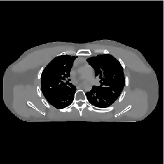

This section compares the generalization capabilities between the proposed MBIR method, PWLS-ST-, and a denoising deep NN, FBPConvNet [14], that are trained from the phantom data; in particular, we tested the trained PWLS-ST- and FBPConvNet models to phantom and clinical scan data. The results in Fig. 6 show that the non-MBIR FBPConvNet method has higher overfitting risks, compared to the proposed PWLS-ST- MBIR method. When tested on clinical scan data, PWLS-ST- achieves much more accurate reconstruction, compared to FBPConvNet. See Fig. 6(b). When tested on phantom data, FBPConvNet generates more unnatural features as the number of views reduces, although it gives lower RMSE values compared to PWLS-ST-. See zoom-ins in Fig. 6(a). The FBPConvNet results above correspond to those in the recent work [16] that FBPConvNet [14] generated some unexpected structures.

| FBPConvNet (Jin et al., 2017) | Proposed PWLS-ST- | Reference | |

| % () views | |||

| (a) XCAT phantom data | |||

| (b) GE clinical data | |||